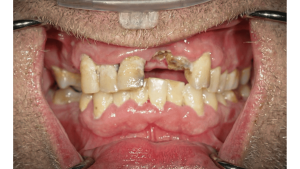

Patient Presentation

A 76-year-old male presented with generalized caries and fractured, non-restorable maxillary teeth. His chief complaint was esthetics and difficulty in chewing.

Guided Surgical Workflow

The case employed the MagnetiX™ Guided Full Mouth Rehabilitation (GFMR) system, composed of:

- After flap reflection and selective extractions, the PPG and BRG were placed and stabilized with fixation pins.

- Remaining teeth were extracted, and bone reduction was performed using the BRG.